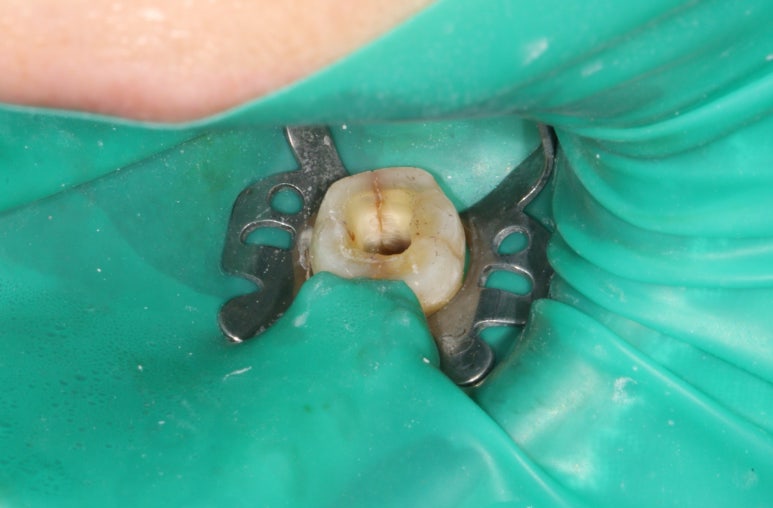

레진치료를 해드리고 얼마 지나지 않은 어느 날, 너무 아프다고 하시면서 내원하셔서 응급 신경치료를 시작하였습니다.

저희 치과에서는 신경치료는 역시, 치과보존과 선생님이 전담해서 전문의 진료를 해주고 계십니다!

신경치료를 시작하기 위해 만들었던 입구를 통해, 세로로 형성된.. 그리고 오래되어 착색까지 된 진한 crack line을 관찰할 수 있었습니다.

치아 크랙은 보통 통증의 history가 길고, 통증이 전기오르듯 찌릿하다 합니다. 이렇게 신경치료를 하고 내부를 확인하여 확신을 얻을 수 있습니다. 다만, 모든 치아를 구멍낼 수는 없겠죠..?